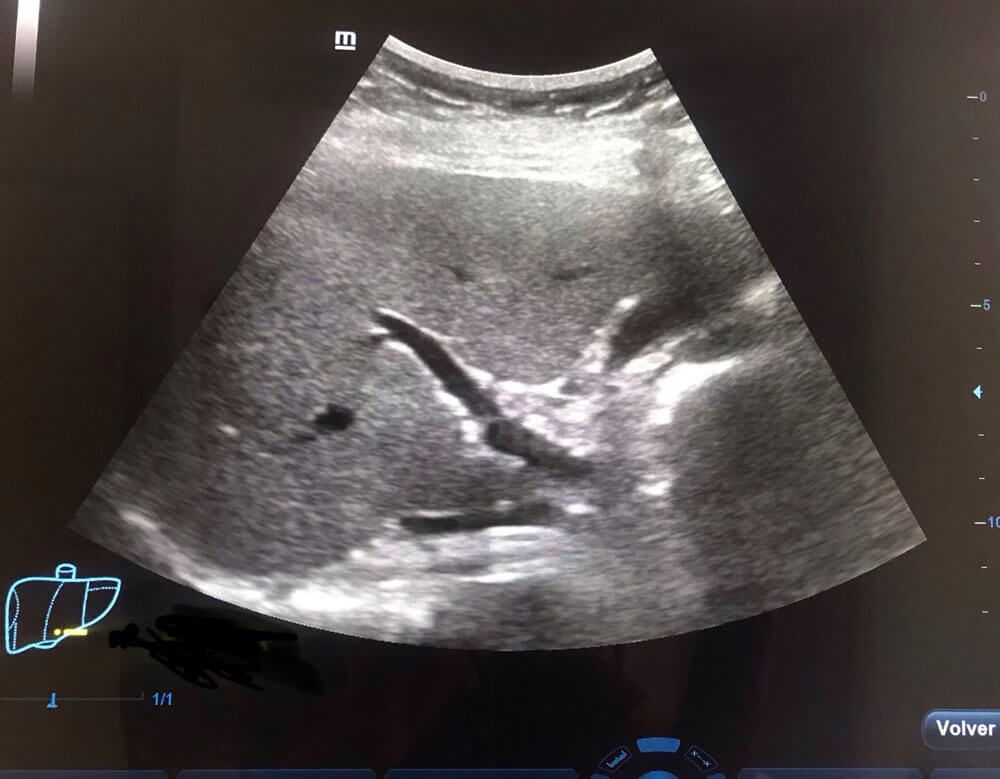

Realizamos

ultrasonidos

convencionales, gestacionales, pediátricos, especializados, entre otros. También aplicamos estudios con